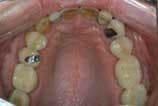

Let me cite a real-life case as an example. (The full-face photo in this case is eliminated for the sake of the patient's privacy.) As we — the patient, my assistant, and I — reviewed the pictures, the patient first noted the brightness of the old porcelain fused to metal crown on his lateral incisor. Then, in the close-up smile photo, he noted the contrast between that tooth and the cuspid behind it. (Figure 1). When he saw the retracted view, it was obvious even to this nondentist that there was something very wrong with his lower plane of occlusion. (Figure 2). He also noticed the exposed PFM margins. This allowed us to explain how the supra gingival margins of Empress restorations would not develop this problem down the road. In the upper occlusal photo, the hole in the crown and the fractured crowns were very apparent, as was the wear and old fillings on his front teeth. (Figure 3.) The wear and irregularities of the lower teeth were also obvious to him. (Figure 4.)